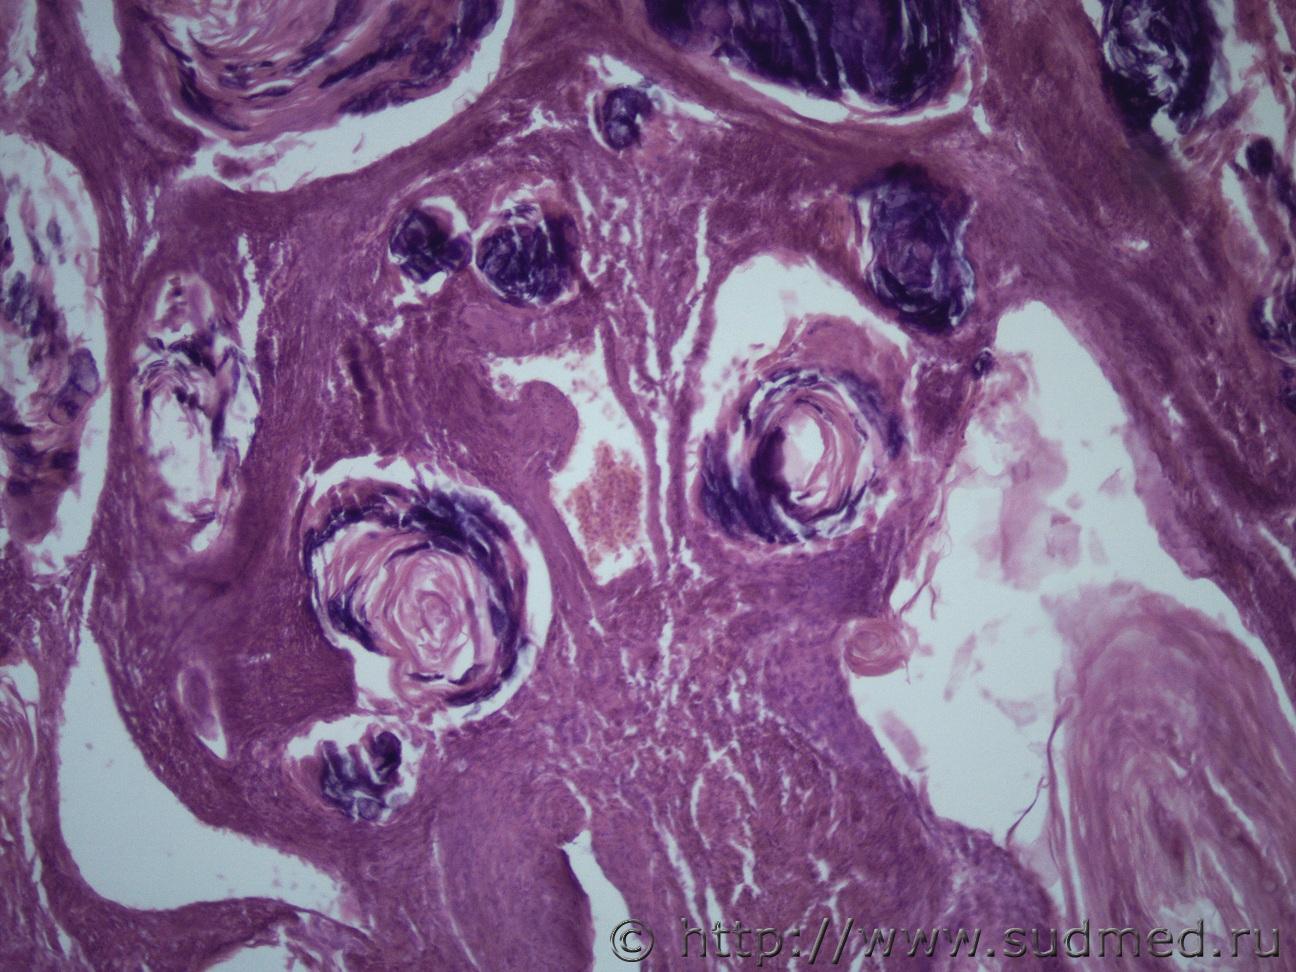

И еще одна опухоль матки жен 1969 г.рСудебная медицина - Прикрепленное изображение Судебная медицина - Прикрепленное изображениеСудебная медицина - Прикрепленное изображениеСудебная медицина - Прикрепленное изображениеСудебная медицина - Прикрепленное изображение

Плоскоклеточный умереннодифференцированный рак,инвазия в железы.

Согласен! Наблюдается ороговение в виде жемчужин.